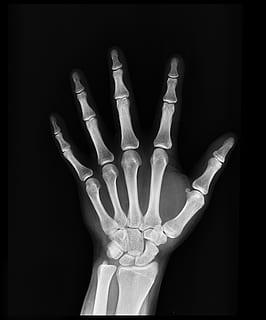

HD wallpaper: bone x-ray result, radiography, diagnosis, anatomy, injury, radiology - Wallpaper FlareLa radiografía de extremidades es una técnica de diagnóstico que se utiliza para visualizar los huesos y las articulaciones de las piernas y los brazos. Esta técnica permite detectar problemas como fracturas, desviaciones, enfermedad ósea y artritis.

Una radiografía de extremidades se realiza mediante la exposición de una parte del cuerpo a los rayos X. Los rayos X pasan a través del cuerpo y son capturados por una placa radiográfica, creando una imagen de los huesos y las articulaciones. Esta imagen se puede visualizar en un monitor y utilizar para determinar el diagnóstico del paciente.

File:Hospital Radiology Room Philips DigitalDiagnost Digital Radiography System.jpg - WikipediaHay varios tipos de radiografías de extremidades, cada uno se utiliza para visualizar diferentes áreas del cuerpo. Por ejemplo, una radiografía de mano se utiliza para visualizar los huesos de las manos y las articulaciones. Una radiografía de pie y tobillo se utiliza para visualizar los huesos de los pies y las articulaciones del tobillo.